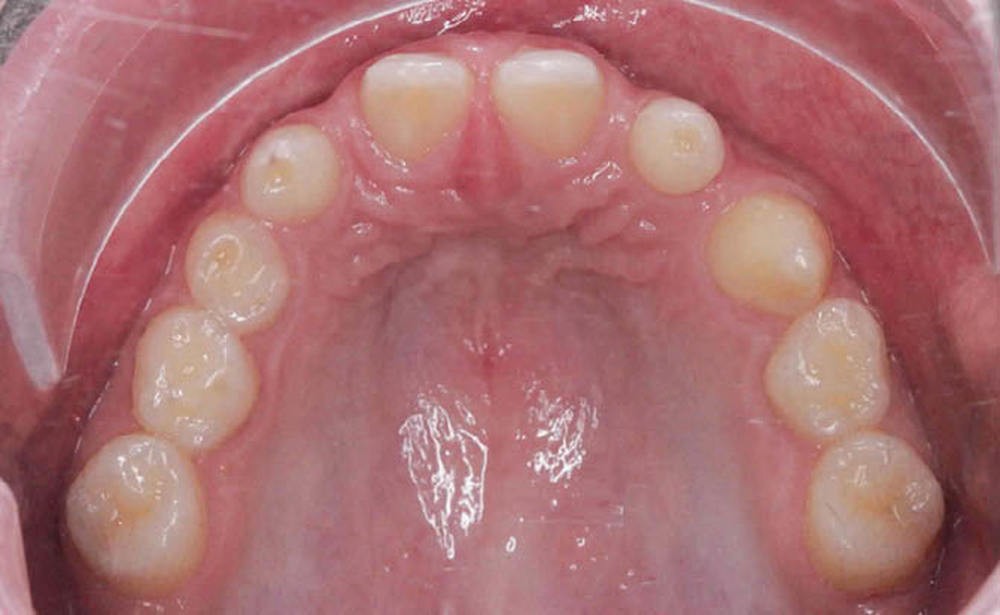

L’orthodontiste réalise des photos ainsi qu’un bilan radiologique complet et le communique au laboratoire (fig.1 a, b).